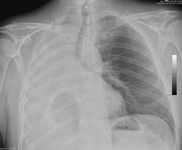

Chest x-ray showing right mainstem endobronchial stent occlusion with mucus

From the collections of Jose Fernando Santacruz MD, FCCP, DAABIP and Erik Folch MD, MSc; used with permission